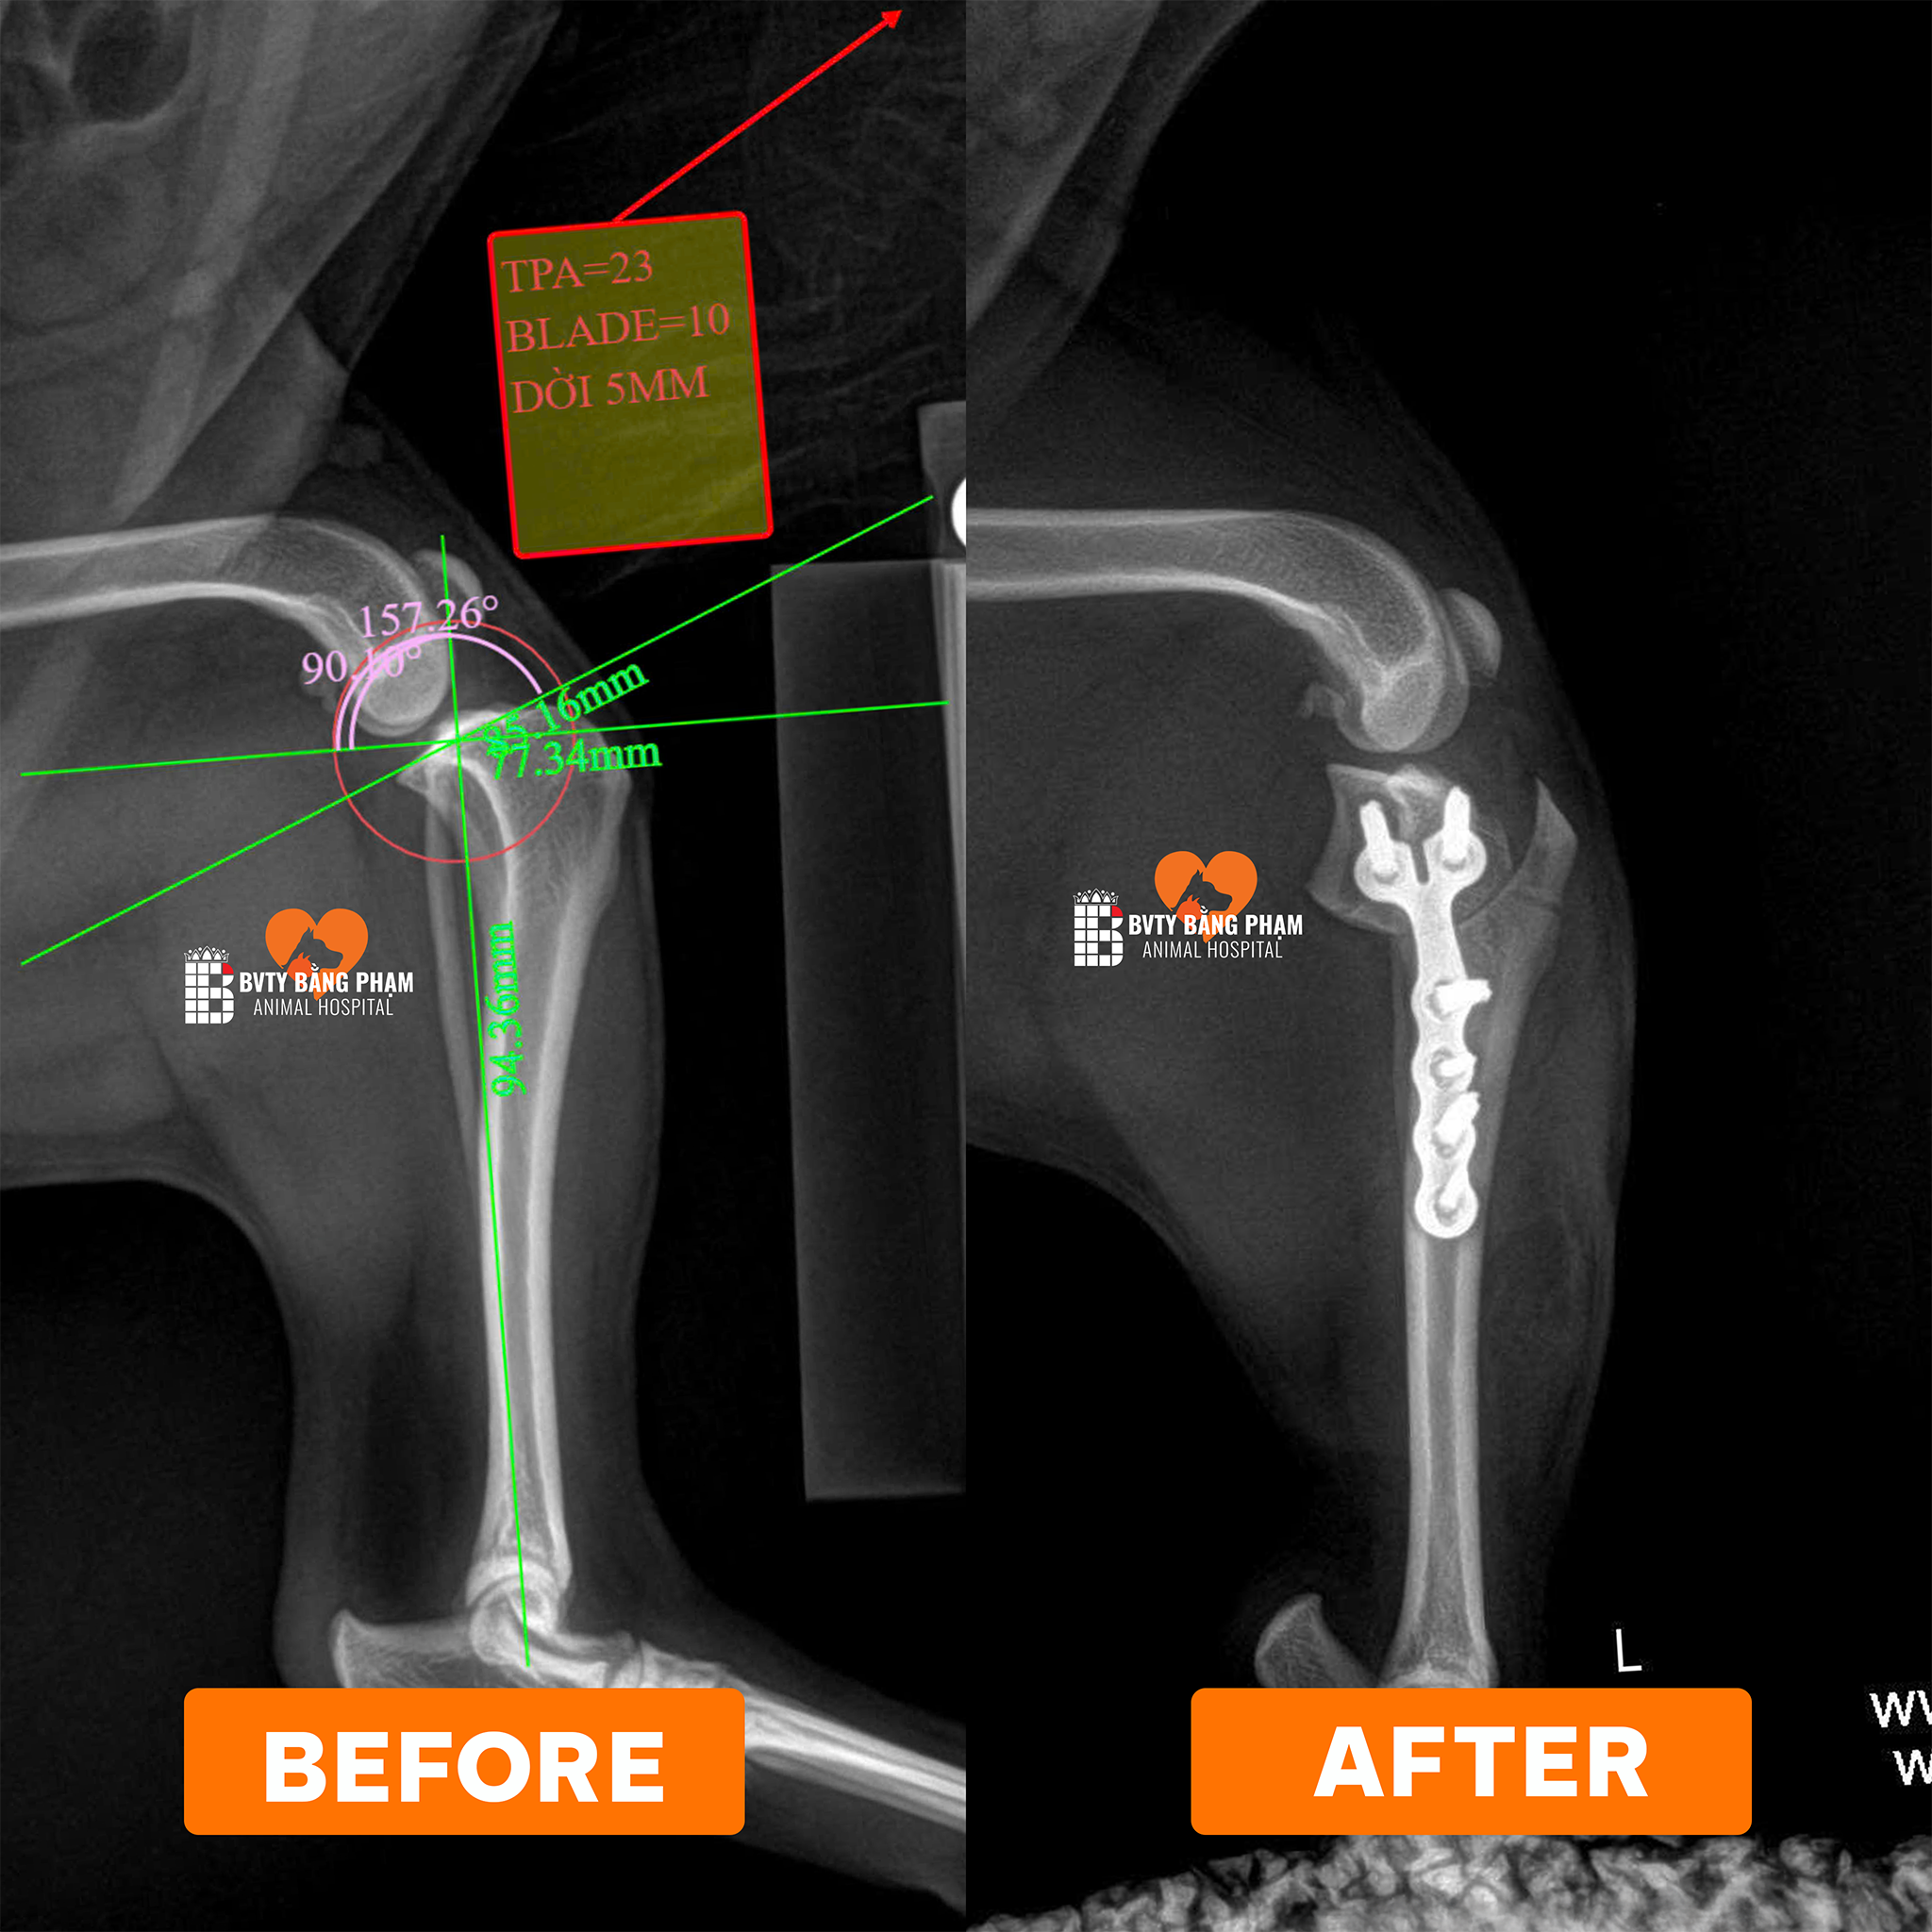

Dịch Vụ Phẫu Thuật

Thực hiện phẫu thuật chỉnh hình xương khớp và thần kinh – cột sống bằng kỹ thuật hiện đại, giúp thú cưng phục hồi vận động và nâng cao chất lượng sống.

Chó Đi Khập Khiễng Chân Sau Là Bệnh Gì? Có Phải Đứt Dây Chằng? Phân Biệt Ngay!

Chó đột ngột đi khập khiễng chân sau? Đừng chủ quan! Đó có thể là dấu hiệu đứt dây chằng...